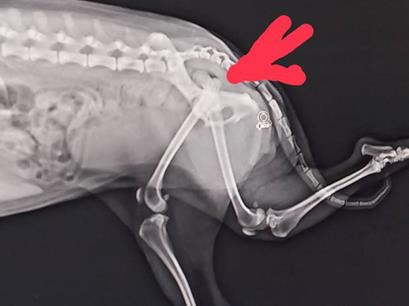

トマト畑の土寄せし、9時半過ぎ近くの動物病院(チェンマイ―メーリム)へ

脱臼と言われ手術と それに耐えられないだろうと・・・ 時間が10時過ぎだったので久々にランナー(クンレック)

パソコンで今日のまとめするも、相棒ルンちゃん 直ってくれると良いのだがなー・・・

夕食前だが動こうとしなくてマットの上で寝ているのか―・・・

17時過ぎ夕食 呼ばなくても来るが自分の席椅子に飛び乗れない! 無理してはいけないのは自分も同じなんだが・・・

ルン ご飯はお昼の分も含めて少し多くだが完食 明日の散歩をどうするかだなー 22時消灯